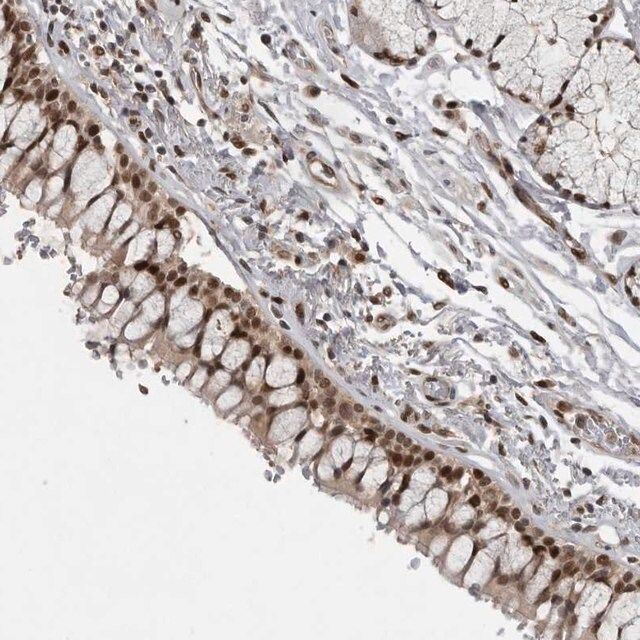

The Human Protein Atlas project can be subdivided into three efforts: Human Tissue Atlas, Cancer Atlas, and Human Cell Atlas. The antibodies that have been generated in support of the Tissue and Cancer Atlas projects have been tested by immunohistochemistry against hundreds of normal and disease tissues and through the recent efforts of the Human Cell Atlas project, many have been characterized by immunofluorescence to map the human proteome not only at the tissue level but now at the subcellular level. These images and the collection of this vast data set can be viewed on the Human Protein Atlas (HPA) site by clicking on the Image Gallery link. To view these protocols and other useful information about Prestige Antibodies and the HPA, visit sigma.com/prestige.

| technique(s) | immunoblotting: 0.04-0.4 μg/mL immunofluorescence: 0.25-2 μg/mL immunohistochemistry: 1:20-1:50 |